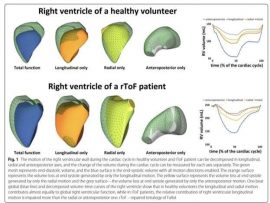

Read MoreAbstract Background Data about the right ventricular (RV) mechanics adaptation to volume overload in patients with repaired tetralogy of Fallot (rToF) are limited. Accordingly, we sought to assess the mechanics..